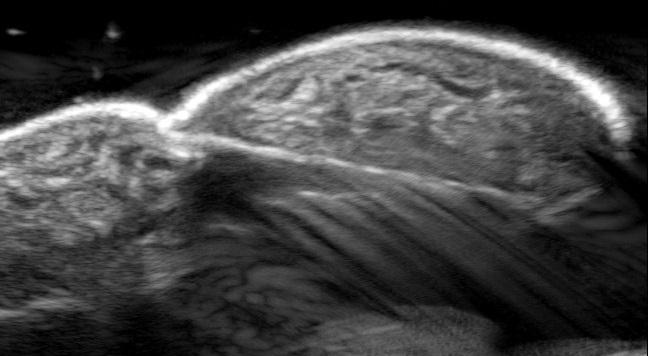

Een 45-jarige man komt op de SEH vanwege aanhoudende pijn aan de rechter wijsvinger. Enkele uren eerder heeft hij een houtsplinter uit diezelfde vinger verwijderd. Hij vermoedt dat er een rest is achtergebleven. Bij lichamelijk onderzoek heeft hij een klein wondje aan de vinger. Omdat de splinter niet meer te zien of te voelen is, wordt een echo gemaakt.